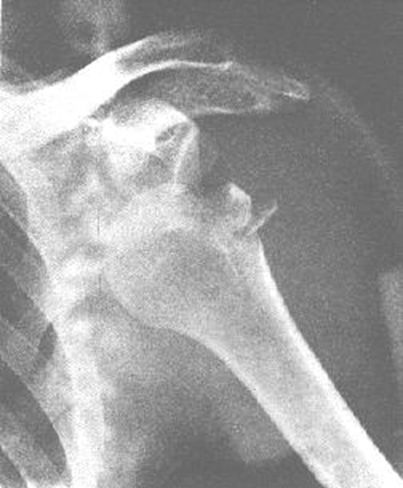

正常肩关节

肩锁关节脱位

肱骨外科颈骨折

内收或外展型损伤–最常见–骨折线为横行,伸展型损伤–间接外力引起–骨折线横行,向前成角,屈曲型损伤:较少见。